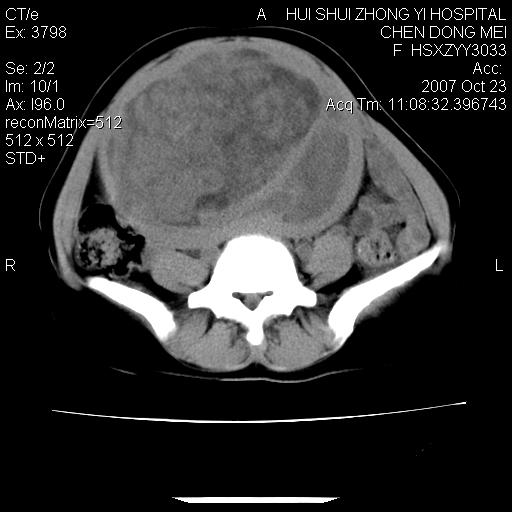

标题: CT10156:女.43岁,发现中下腹部包都块2年 [打印本页]

标题: CT10156:女.43岁,发现中下腹部包都块2年

发现中下腹部包都块2年。2年来月经不规律。

腹腔巨大软组织密度影,边缘光滑,包膜完整,内囊变坏死。腹膜后及盆腔内淋巴结肿大。结合病史考虑卵巢癌可能性大。

病灶内可见脂肪密度影,考虑畸胎瘤可能性大

病变巨大,呈囊实性改变,包膜较厚且完整,内见分膈,周围脏器明显受压移位,病变与左侧附件关系密切,考虑来源左侧附件的囊腺瘤,不除外癌变可能;畸胎瘤可能性较小。

病变巨大,呈囊实性改变,包膜较厚且完整,内见分膈,周围脏器明显受压移位,病变与左侧附件关系密切,考虑来源左侧附件的囊腺瘤,盆腔内见肿大淋巴结,不除外癌变可能。

病变巨大,呈囊实性改变,包膜较厚且完整,内见分膈,周围脏器明显受压移位,病变与左侧附件关系密切,考虑来源左侧附件的囊腺瘤,不除外癌变可能